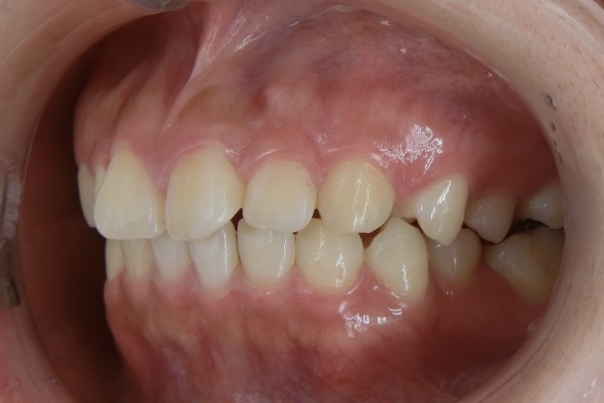

BEFORE

20代女性 すきっ歯が気になる

20代女性の患者さまで、4人のお子さまを育てながら、できるだけ目立たない方法ですきっ歯を治したいとご相談に来院されました。子育てや日常生活への影響をできる限り抑えながら治療を進めたいというご希望を踏まえ、当院で専門的に行っているマウスピース矯正にて治療を進めました。